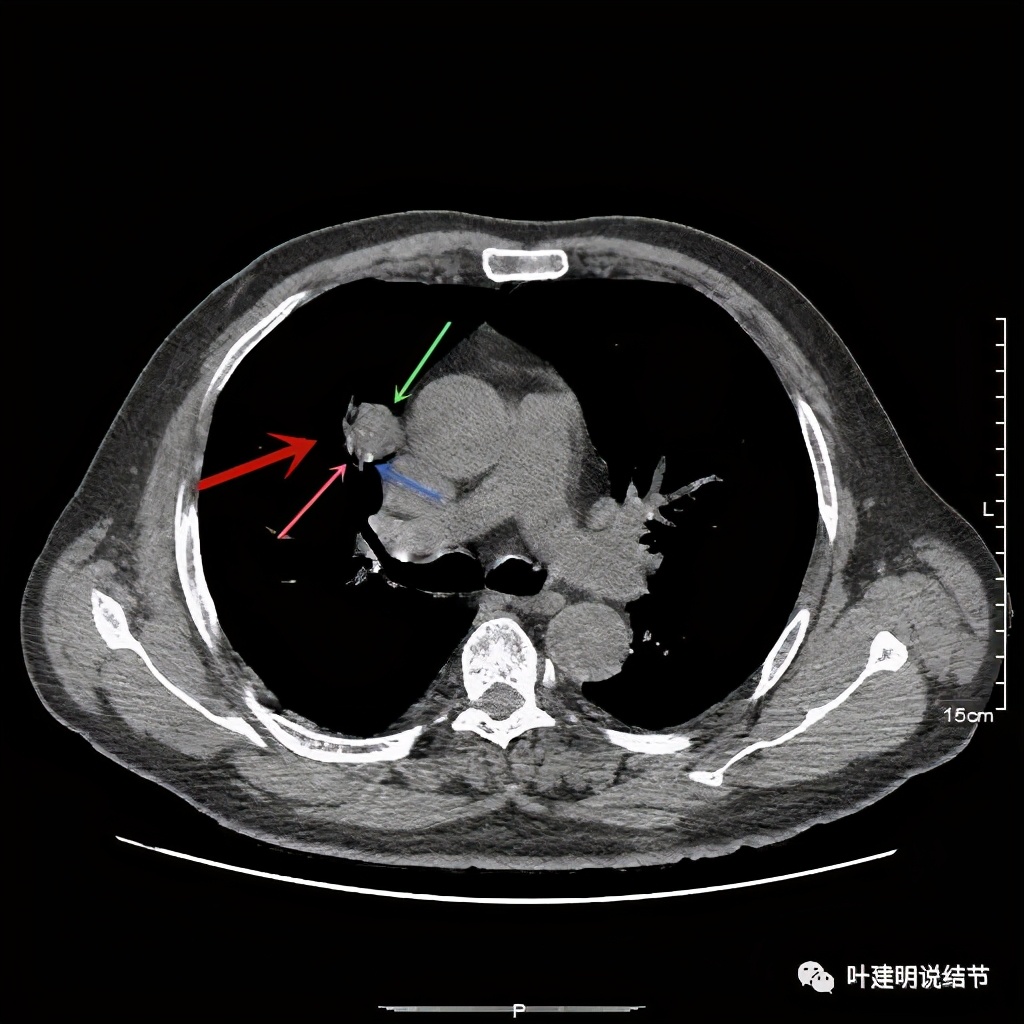

上图也示病灶密度不均,但边缘过于光滑(绿色);支气管似有截断(粉色);局部有点状钙化(蓝色)

病灶在上图层面似见支气管也是贴壁的。那么增强后又是如何呢?

上图示病灶边缘过于光滑(绿色);局部有点状钙化(蓝色)